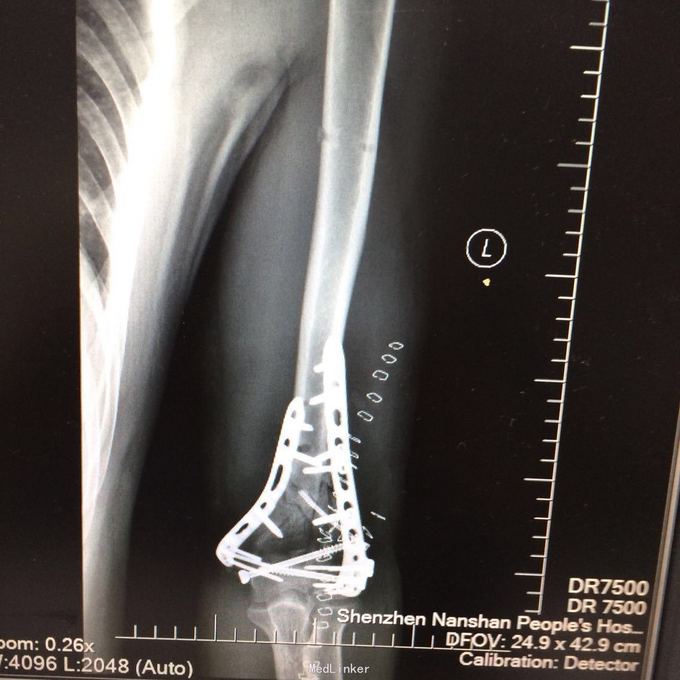

1、左肱骨远端粉碎性开放性骨折;2、左肘关节半脱位;3、左手第4、5掌骨远端骨折;4、右手第1、3、4远节指骨骨折;5、右手第5中节、远节指骨骨折;6、鼻部软组织挫裂伤;鼻中隔骨折;7、右侧第3--7肋骨折;8、左跟骨粉碎性骨折;9、左眉弓软质挫裂伤;10、左肺挫伤;11、脑震荡。 1.完善三大常规、PT四项、生化等各项常规检查; 2.完善CT检查,予抗破伤风、抗感染、镇痛、止血等对症支持治疗; 3.请口腔、耳鼻喉、眼科等相关科室会诊; 4.请示上级医师,指导下步治疗。 手术时间:2015年11月15日 术后诊断:左肱骨远端开放性粉碎性骨折 麻醉方式:全身麻醉 手术名称:左肱骨远端开放性粉碎性骨折清创缝合外固定架固定术 手术时间:2015年12月25日 术后诊断:左肱骨远端粉碎性骨折 麻醉方式:臂丛麻醉 手术名称:左肱骨远端粉碎性骨折切开复位内固定术 。 手术时间:2015-12-3 术后诊断:左跟骨粉碎性骨折;左肱骨远端粉碎性开放性骨折;左肘关节半脱位;左手第4、5掌骨远端骨折;右手第1、3、4远节指骨骨折;右手第5中节、远节指骨骨折;右足拇趾撕脱骨折并趾间关节脱位;鼻部软组织挫裂伤;鼻中隔骨折;右侧第3--7肋骨折;左眉弓挫裂伤;左肺挫伤;脑震荡。 麻醉方式:腰硬联合 手术名称:左跟骨粉碎性骨折切开复位钛板内固定术

术后处理措施及注意事项:防止出血、镇痛,注意观察肢端感觉及血运,给予抗炎、消肿、补液等对症综合处理。